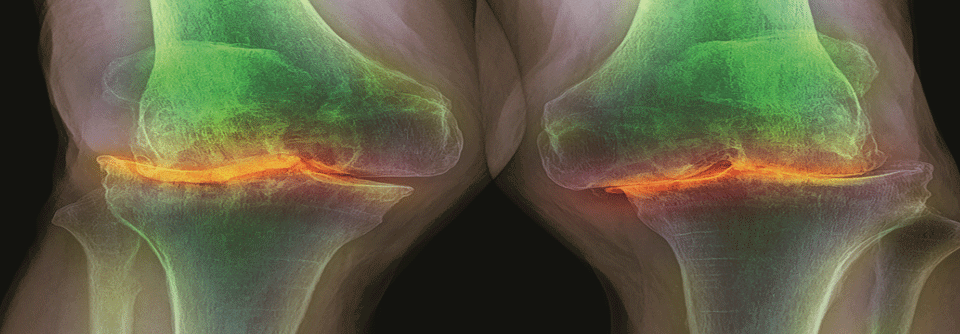

Eine gründliche Anamnese für eine saubere Differenzialdiagnostik ist bei der Monarthritis unerlässlich. Eine gründliche Anamnese für eine saubere Differenzialdiagnostik ist bei der Monarthritis unerlässlich. © anut21ng Stock – stock.adobe.com